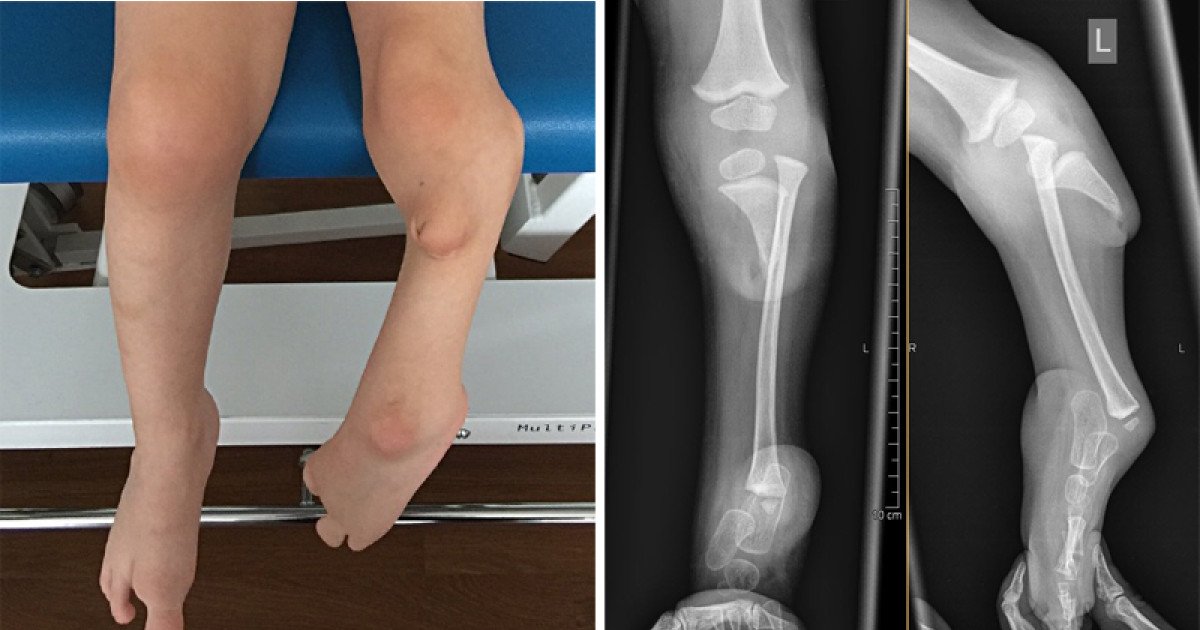

Congenital Amputee